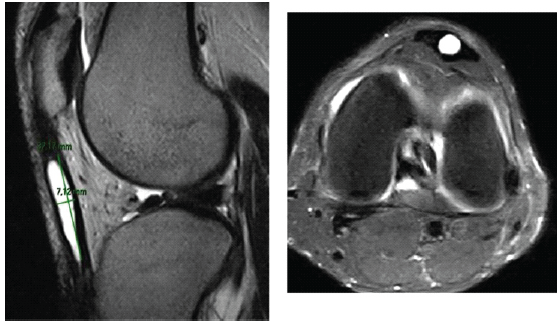

MRI revealed a well-circumscribed, multilobulated cystic lesion – hypointense on T1-weighted and hyperintense on T2-weighted sequences – located within the substance of the patellar tendon, measuring 2.5 × 1.5 × 1.2 cm. The lesion showed no communication with the knee joint cavity. Surrounding tendon fibers appeared intact, with no evidence of rupture or inflammatory changes (Fig. 2).